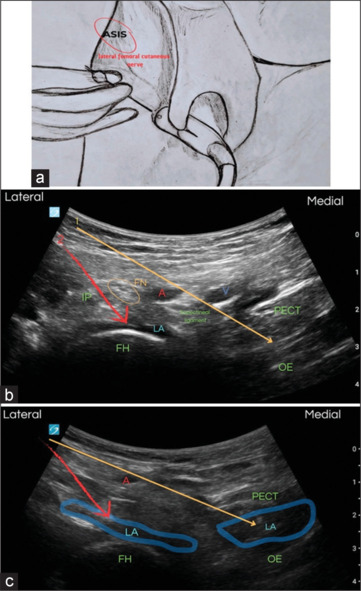

Femoral rami obturator nerve trunk (FRONT) block in intramedullary nailing surgery: A motor-sparing approach to anterior hip analgesia.